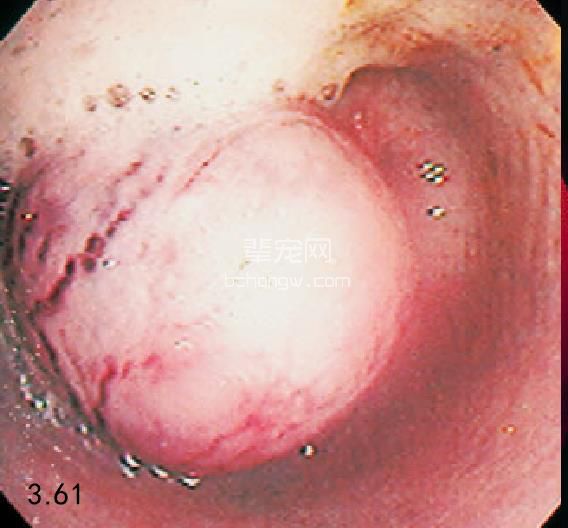

病因学 病因包括狭窄、异物、肿瘤以及较少见的憩室和胃食管套叠。原发性食管肿瘤包括平滑肌瘤、癌 和肉瘤(图3.60~图3.63)。有一篇报道称转移性甲状腺肿瘤是最常见的食管肿瘤。胃前部的癌症也可能影响到 食管下括约肌和后段食管。酸性物反流(特别是麻醉期间)、食管异物取出后的狭窄是造成食管狭窄的主要原 因。对于犬和猫来说,最常见的食管异物是骨头。食管憩室是由食道内力(异物)破坏食管完整性后形成的。 最容易出现憩室的位置是胸腔入口和膈上的区域。

图3.61 一只10岁德国牧羊犬食管内无症状的平滑肌瘤。